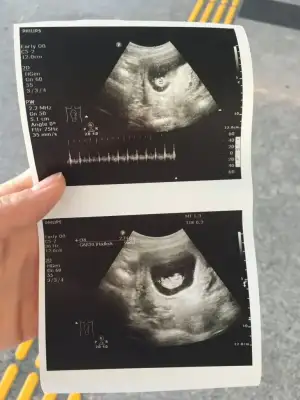

Karindan ise erkek gorunuyor vajinal ise kizIkra meyra canım bakabılır mısın 5+5 haftalık

Teşekkürler canım kesede ki konumuna göre mi anlıyorsunuzKadından ise erkek gorunuyor vajinal ise kiz

Kadından ise erkek gorunuyor vajinal ise kiz

Kese konumu pek tutmuyor karından ise erkek gorunuyor vajinal ise kız6 haftalık iken şuan 11 haftalık